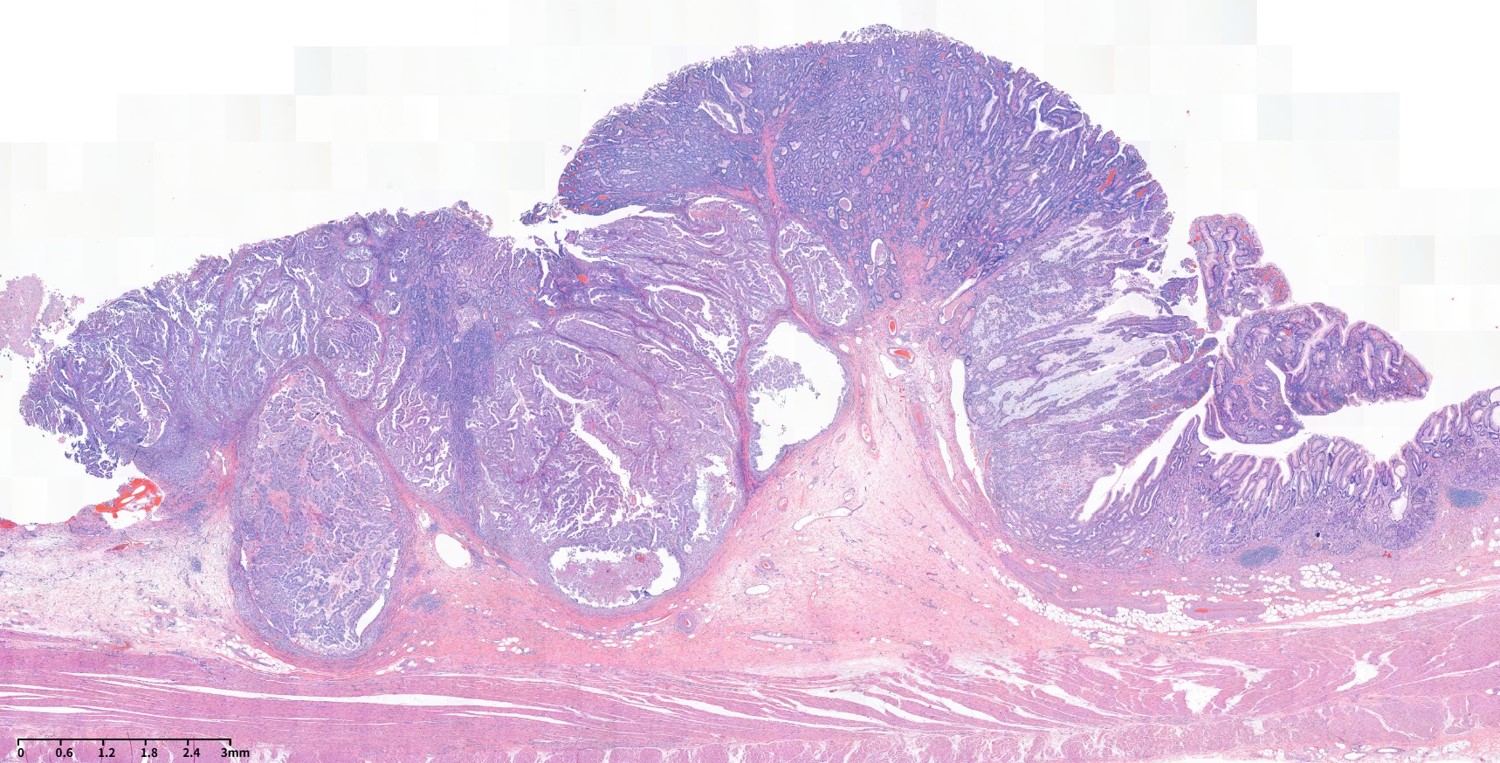

¿¬¼Ò¼º ¿ëÁ¾Àº ³»½Ã°æÀûÀ¸·Î ¹ÝÁú¹ÝÁúÇÏ°í ºÎµå·¯¿î Ç¥¸éÀ» °¡Áö°í ÀÖ°í Á¶Á÷ÇÐÀûÀ¸·Î ±âÁú ¼¼Æ÷¿¡ µÑ·¯ ½ÎÀÎ ³¶¼º Á¶Á÷ÀÌ Á¡¾×À¸·Î °¡µæ Â÷ ÀÖ´Â ¸ð¾çÀ» º¸À̴µ¥ ÆòȰ±ÙÀÇ Áõ½Ä¿¡¼­ ¹ß»ýÇÏ´Â °ÍÀÌ ¾Æ´Ï±â ¶§¹®¿¡ ÁøÁ¤ÇÑ ÀǹÌÀÇ °ú¿ÀÁ¾ÀÎÁö´Â ¸íÈ®ÇÏÁö ¾Ê½À´Ï´Ù.

ÇÑ ÀϺ» Ã¥ ¹ø¿ªº»¿¡¼­ °¡Áö°í ¿Â ³»¿ëÀÔ´Ï´Ù. ½âÀº µþ±â ¸ð¾çÀ̶ó´Â ƯÀÌÇÑ ±â¼úÀÌ ÀÖ¾ú½À´Ï´Ù.